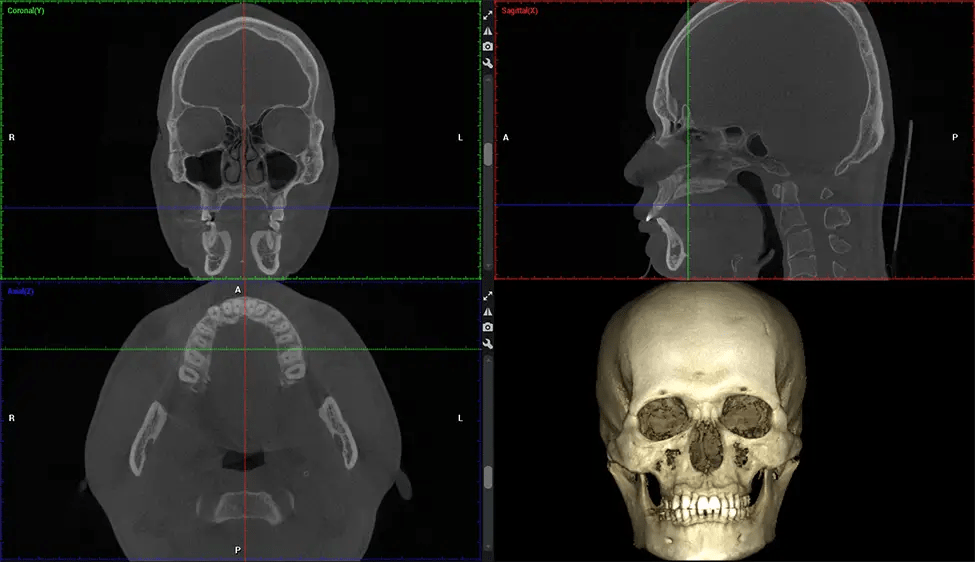

Cone Beam Computed Tomography (CBCT) is an advanced imaging technique used in dentistry and maxillofacial surgery to obtain detailed 3D images of the oral and maxillofacial structures. At Dr G Dental Studio, our CBCT scanners utilize a cone-shaped X-ray beam and a specialized detector to capture images from different angles. A computer then combines these images to create a 3D representation of the patient’s oral anatomy.

This 3D scan, called cone beam computed tomography, gives your dentist a more complete image of your oral anatomy and disease processes than a traditional X-ray. Unlike conventional X-rays, which capture a 2D image of your mouth from various angles, a 3D scan takes multiple digital X-rays for one image. It provides a complete view of your jaw, teeth, nerves, and soft tissues. This enhanced view allows dentists to detect minor issues not visible in traditional 2D scans, such as impacted wisdom teeth or bone fractures in the sinus cavity.

The patient is first positioned in the CBCT scanner, which typically consists of a rotating arm that houses the X-ray source and a detector. The patient’s head is immobilized to ensure accurate image capture. The X-ray source and detector rotate around the patient’s head, capturing various X-ray images from multiple angles. As the X-ray source rotates, it emits the cone-shaped X-ray beam towards the detector. The detector captures the X-ray images, which are then processed by the CBCT software.

After the scanning process, the captured X-ray images are processed by the CBCT software, which applies algorithms to reconstruct a detailed 3D image of the scanned area. The software compiles these individual X-ray images and creates a digital 3D representation of the patient’s anatomy. The reconstructed 3D CBCT image can be viewed and analyzed by the dentist or radiologist. This image can be manipulated, rotated, and zoomed in or out to examine specific structures and evaluate the patient’s condition.

Planmeca Viso G7 CBCT ( Cone Beam CT Scan ) is designed to surpass the demands of industry leaders, specialists, and large institutions. It’s has a large ø25×30 cm sensor with four built-in cameras. It can capture unlimited volume sizes from a ø3×3 cm to a ø30x30cm volume capturing the skullcap through C7 on the cervical spine. The Planmeca Viso G7 offers the industry’s largest single volume scan of ø30×19 cm. It’s poised to handle advanced imaging modalities such as Planmeca ProFace® and Planmeca 4D™ Jaw Motion technology. The occipital head support allows an unimpeded view of facial tissue.